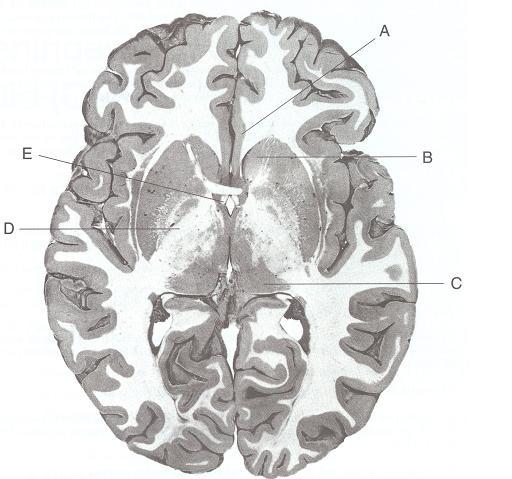

Questions 11-15

Match the structure or description in items 11-15 with the appropriate lettered structure shown

in the stained thick section of the brain.

1. Has reciprocal connections between the hippocampal formation and the septal nuclei

2. Largest nucleus of the diencephalon

3. Internal capsule

4. Cingulate gyrus

5. Caudate nucleus

11-E. The fornix contains fibers from the hippocampal formation and from the septal nuclei, pro-

jects massively to the mamillary nuclei of the hypothalamus, and plays an important part in the

circuit of Papez.

12-C. The pulvinar nucleus is the largest nucleus in the diencephalon.

13-D. The posterior limb of the internal capsule lies between the lentiform nucleus and the thal-

amus. It contains the corticospinal tract and is perfused by the lateral striate arteries of the mid-

dle cerebral artery.

14-A. The cingulate gyrus and its cingulum belong to the limbic system.

15-B. The caudate nucleus and the putamen comprise the striatum, a basal ganglion. In Hunt-

ington disease, massive loss of neurons in the head of the caudate nucleus results in hydro-

cephalus ex vacuo.